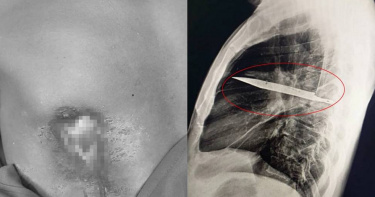

高雄旗山一對父女倒臥車內 女兒胸前2刀喪命、父被送醫搶救中

高雄旗山區今(28)日凌晨2時許發生死亡事件,警方獲報民眾失蹤,從定位發現失蹤人員可能在中寮一路附近,因此派員前往查看,發現一對父女倒臥車內滿手是血,女兒已死亡、父親命危搶救中,初判無外力介入;橋頭地檢署檢察官相驗女兒遺體,發現她前胸中2刀疑為致命傷,下周四將複驗;另案發現場發現數把刀子,已帶回送驗。據了解,該名74歲父親與46歲女兒與母親、兒子住在苓雅區,父女友共同經商,但疑因經營不順背負大量債務,今凌晨0時許苓雅分局警方接獲兒子報案,稱父親留下字條與女兒一起出門徹夜未歸,擔心2人出事,警方透過手機定位掌握到父女在旗山區,立即協請旗山分局緊急協尋。旗山分局警方根據定位,在中寮一路一處空地發現父女所開的銀色轎車,上前查看發現2人手上滿是鮮血,並在車內搜出沾血的水果刀,其中女兒已明顯死亡、父親則尚存一氣,緊急送往醫院搶救,目前尚未脫離險境。警方初判無外力介入痕跡,但為求謹慎報請橋頭地檢署介入調查。橋頭地檢署檢察官李奇哲今上午初驗遺體,目前判定死者主要刀傷在前胸,該女前胸中2刀,疑為致命傷,但仍有待10月2日複驗才能確定死因;另案發現場車內發現數把刀子,目前已經全數帶回送驗。◎勇敢求救並非弱者,您的痛苦有人願意傾聽,請撥打1995◎如果您覺得痛苦、似乎沒有出路,您並不孤單,請撥打1925